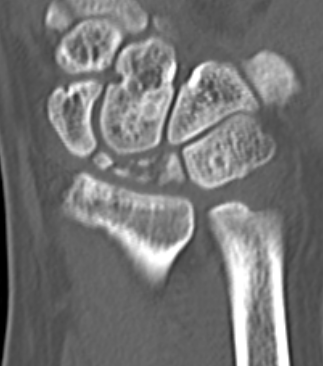

CT

Hesse et al J Hand Surg Eur 2025

- CT more accurate at gauging Kienbock's

- disease frequently worse on CT than assessed on xray

Lunate precollapse

CT demonstrating lunate fragmentation and collapse